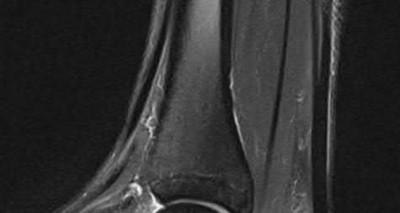

A 25-year-old male sustained a closed midshaft femur fracture following a motor vehicle collision. He is taken to the operating room for supine intramedullary nail fixation of the fracture. Figure A is a lateral fluoroscopic view of the distal femur taken just prior to distal interlocking screw placement. What change in position (with the Carm stationary) would be expected to produce a perfect lateral view of the interlocking hole?

1) Raising the leg

2) Lowering the leg

3) Internal (or external) rotation of the leg

4) Abduction (or adduction) of the leg

5) Fluoroscopic magnification

Interlocking of intramedullary nails using fluoroscopy requires attention to detail. A true lateral of the intramedullary nail is present when "perfect circle" views of interlocking holes are present. Once perfect circles are obtained, the drill can be advanced parallel to the fluoroscopic beam.

Knowledge of the implications of the appearance of the interlocking holes when "perfect circles" are not present can be helpful in minimizing the number of manipulations and fluoroscopic exposure. Widening of the interlocking hole in the proximal-distal direction (as is seen in this case) signifies the need for an adjustment in the abduction/adduction plane. Similarly, widening of the interlocking hole in the anterior-posterior plane signifies the need for an adjustment in the internal/external rotation plane (Answer 3).

Raising or lowering the leg (Answer A and B) should not have major effects of the appearance of the interlocking hole. Similarly, magnification of the C-arm (Answer D) will not affect the appearance. Internal/external rotation will result in widening in the anterior-posterior plane (as this dimension is currently adequate). Abduction or adduction will result in creating "perfect circles" (Answer 4). The position of the leg may hint to which of these is correct. If further widening occurs in the proximal-distal direction, the opposite maneuver will correct to the proper position.